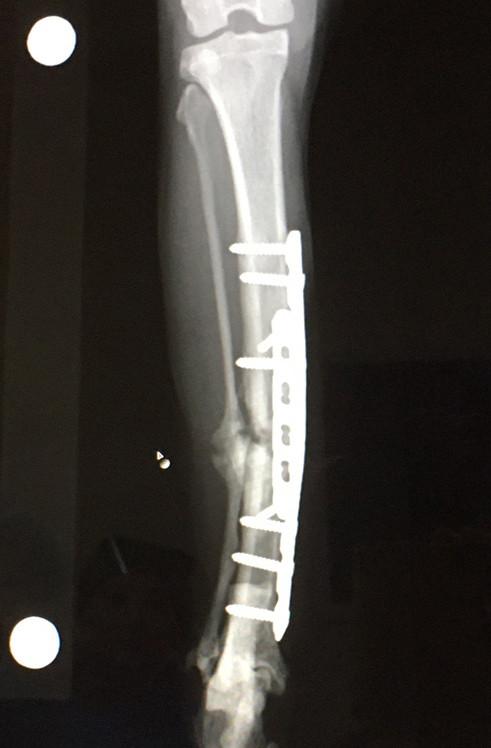

10月4日 手術から約2ヶ月(10週間)後

札幌病院、経過観察、骨形成遅め

10月23日 手術から約3ヶ月(13週間)後

ケージレスト終了

11月29日 手術から約4ヶ月(18週間)後

札幌病院、経過観察、骨形成OK

犬ならこの時点で抜去手術のスケジュール組む時期だけどプレート曲げた猫なので様子見継続。

隔離部屋閉鎖

1月21日 手術から約5ヶ月(25週間)後